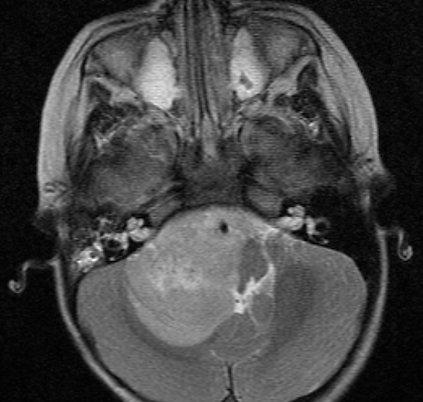

Conor Cockerton

"(Dr Teo) said if we could get a public hospital to send an invitation (he) could do the operation earlier anywhere in Australia. We wrote to public hospitals in Sydney, Melbourne, Perth, Bundaberg, Brisbane, and Townsville, all the hospitals declined.

It was a frustrating time being given different opinions, but I always felt (Dr Teo) had the most experience for me to put my trust in. And I made the right decision.

Thank you again for giving me my life back when others refused."